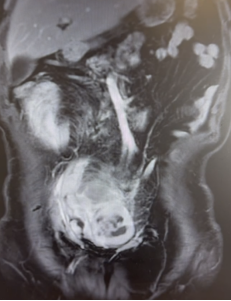

56岁男性患者,因间断上腹不适4个月,检查发现腹膜后肿瘤2周。腹部CT及核磁提示腹膜后巨大脂肪肉瘤,直径约35cm。

我们为患者实施全麻下开放腹膜后肿瘤切除术。术中可见肿瘤挤压十二指肠、胰头、肠系膜血管、下腔静脉和腹主动脉,但未侵犯结肠、肠系膜血管等组织器官,且包膜完整。手术团队仔细游离,完整切除腹膜后肿瘤,剔除腹膜后脂肪。历时2个小时完成,术中出血约100ml。

术后恢复顺利:第3天排气并进食流食;第5天恢复正常饮食;术后第9天出院。术后病理高分化脂肪肉瘤,肿瘤最大径38cm,与肾周脂肪粘连。术后3月随访,未见肿瘤复发。